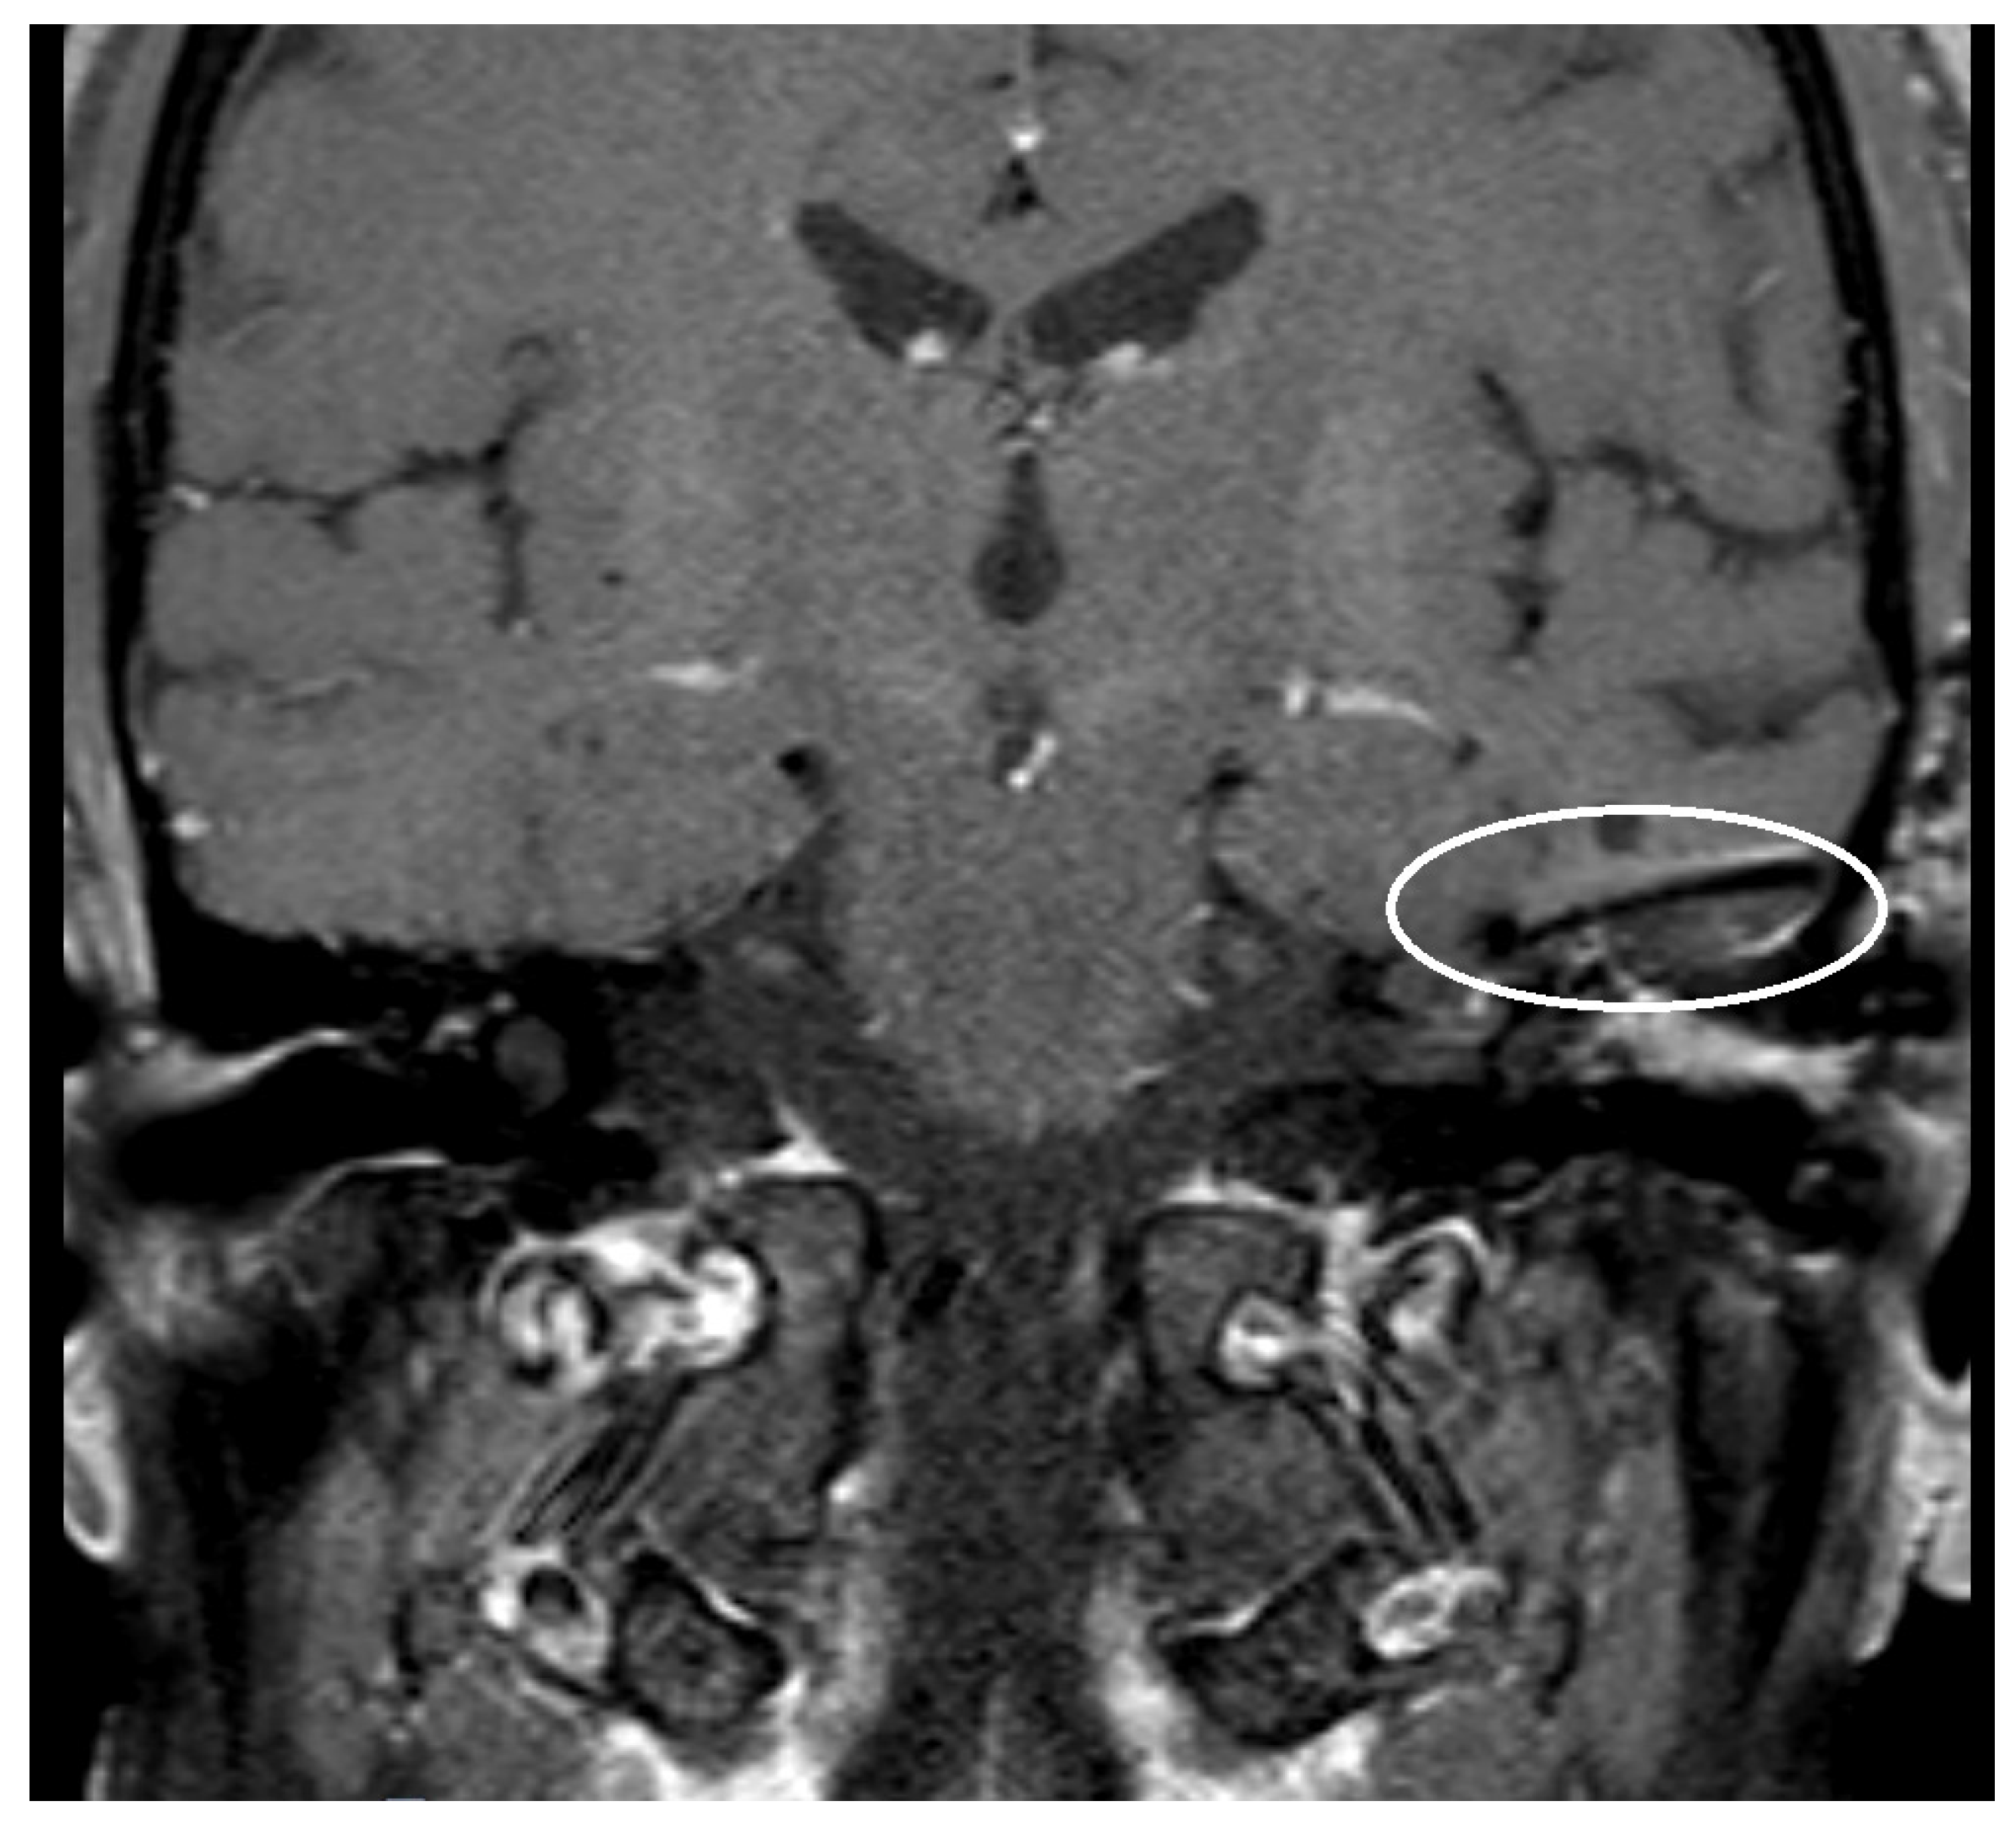

| Size of artifact | 3.60 (sd = 1.01, min = 2.50, max = 4.50) | 3.11 (sd = 0.54, min = 2.20, max = 4.50) | 4.74 (sd = 0.77, min = 3.90, max = 6.10) |

| PORP | 2.0 mm | 3.1 mm | 5.4 mm |

| TORP | 3.6 mm | 4.7 mm | 7.2 mm |

| Mesh | 0.1 mm | 3.6 mm | 5.8 mm |